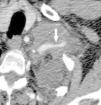

Pese a las conocidas limitaciones de la TC, ésta continúa siendo la técnica de elección en la estadificación del tumor en los pacientes con CPNM; su sensibilidad y especificidad en la determinación de la infiltración de pared oscilan entre el 38 y el 87% y del 40 al 90%, respectivamente, según las series. El desarrollo de nuevos equipos de TC helicoidal y principalmente las TC multidetectoras (TCMD) proporcionan unas imágenes 2D de mayor resolución con la posibilidad de hacer reconstrucciones multiplanares (MPR) en distintos planos del espacio e incluso 3D con la consiguiente mejora de la valoración del tumor, su extensión e infiltración de estructuras vecinas5 (fig. 4). Así, con la TCMD se puede poner de manifiesto con mayor fiabilidad la invasión de la cisura, la pared torácica o el mediastino, y además es capaz de determinar, gracias a las reconstrucciones de volumen, la relación exacta del tumor con la vía aérea (fig. 5). El progreso en la capacidad diagnóstica deriva del incremento en la resolución de las imágenes obtenidas y de la posibilidad de emplear nuevas aplicaciones como la broncoscopia virtual y la visualización en tiempo real. La broncoscopia virtual es útil para valorar la invasión del árbol traqueobronquial con la finalidad de planificar la cirugía, también como guía para el fibrobroncoscopista y, por último, porque permite ver el árbol bronquial distal a la estenosis (fig. 6)6. La capacidad de ver la imagen en tiempo real es especialmente útil cuando se emplea como guía en maniobras intervencionistas como biopsias percutáneas, ya sea con finalidad diagnóstica o como parte de la estadificación (fig. 7). Esta técnica de guía de biopsia denominada TC fluoroscopia reduce el número de pases y el tiempo global de la exploración, implica un menor riesgo de lesión de estructuras y permite la visualización inmediata de las posibles complicaciones7.

Fig. 4.--Invasión vascular. Tomografía computarizada (TC) torácica con contraste. Corte axial (A) y reconstrucción coronal oblicua (B). Invasión tumoral por continuidad de la vena pulmonar inferior (flecha).